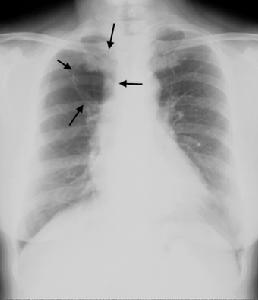

2.單個氣囊腫:胸片上示病側肺部含氣囊腫,巨大的氣囊腫可占據一側胸腔,壓迫肺,氣管,縱隔,心臟,需與氣胸鑑別。氣胸的特點是肺萎縮推向肺門,而氣囊腫的空氣位於肺內,往往仔細觀察在肺尖和肋隔角處可見到肺組織。

縱隔支氣管囊腫診斷主要依靠胸部X線檢查,表現縱隔部位圓形或類圓形邊緣光滑或銳利的均勻一致的緻密陰影。CT等有助於鑑別肺與縱隔及周圍重要器官的關係。囊腫較大時纖維支氣管鏡,食管鋇透檢查可顯示相應部位的氣管、支氣管或食管受壓情況。如囊腫與氣管或支氣管相通,囊腫內可見液平。有時在X線透視下囊腫可隨吞咽運動上下活動或變形,囊腫超聲可以鑑別囊內液體的性質,以排除血管性腫物。縱隔支氣管囊腫術前確診比較困難。